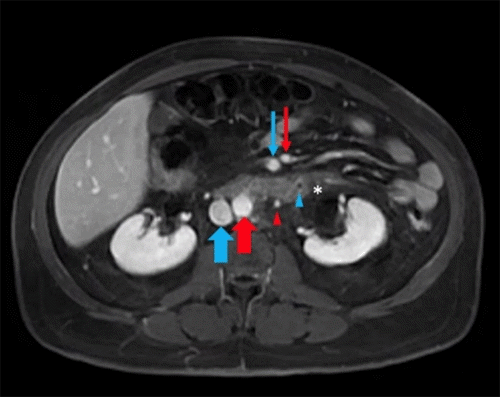

Computed tomography (CT) abdomen/pelvis with contrast demonstrated thrombophlebitis involving at least two branches of the IMV, one of which led to the sigmoid colon (Figure 1A). There was no extension into the portal vein. Mild sigmoid diverticulitis without paracolic abscess or free air was noted. Magnetic resonance imaging (MRI) abdomen/pelvis with contrast demonstrated filling defect of the IMV nearly to its confluence with the splenic vein; rectal wall and perirectal fat inflammation; and subacute sigmoid diverticulitis with lateral tethering to the abdominal wall (Figure 1B). Reactive inflammation of the left ureter and the perinephric region was also visualized.

Figure 1. CT and MRI Scans. Published with Permission

A) CT of resected sigmoid colon segment with diverticulitis (white arrow) and scattered diverticulum

. B) Magnetic resonance imaging venous phase depicting inferior mesenteric vein with filling defect (blue arrowhead) and surrounding inflammation (white asterisk). Inferior mesenteric artery (red arrowhead), superior mesenteric artery (thin red arrow), superior mesenteric vein (thin blue arrow), aorta (thick red arrow), and inferior vena cava (thick blue arrow) labeled for reference.